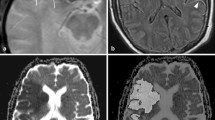

An example of imaging data is shown in Figure 1. The DWI abnormality appears stable at 4 hours after the initial scan, but it increases substantially at 24 hours. The perfusion deficit is much larger than the DWI abnormality, and appears similar at baseline and 4 hours. It becomes smaller at 24 hours, but remains larger than the DWI lesion, indicating relative stability of the region of 'mismatch' over 24 hours. DWI images from each patient at the level of maximum growth are shown in Figure 2. DWI lesions did not change in most patients at 4 hours after baseline. However, most did show a clear increase in volume by 24 hours after baseline.

Imaging data from a patient with a left hemiparesis. Diffusion weighted images (top row) and mean transit time (bottom row) at the level of the lateral ventricles from a patient who presented 4.2 hours after onset of a left hemiparesis, and who was found to have a proximal right middle cerebral artery occlusion by CT angiography. Thrombolytic therapy was not given, but normobaric oxygen was provided by face mask for 4 hours. The image abnormalities were located within the right middle cerebral artery territory. The sizes of the diffusion and MTT abnormalities are very similar at the first 2 time points and there is a large mismatch. At 24 hours after baseline imaging, a large increase in the abnormal diffusion volume is apparent accompanied by a decrease in the abnormal MTT volume, but a greater than 20% mismatch persists. At 1 week, continued increase of the abnormal DWI is observed.

While there is general agreement with respect to DWI, there is much more variability in the perfusion parameter employed. There are several parametric maps that may be generated by analyses of dynamic contrast MRI studies including cerebral blood volume (CBV), cerebral blood flow (CBF), mean transit time (MTT), time to peak (TTP), time to peak of the residue function (Tmax) [10], and others. The deconvolution method employed in the study here uses an arterial input function to derive MTT and CBV, and CBF is calculated (it is equal to CBV/MTT). MRI derived CBF values correlate highly with 15O-water positron emission tomography and have been used to identify penumbral flow [11]. The MTT analysis is the most sensitive for identifying tissues with altered hemodynamics including areas of true ischemia, benign oligemia and fully compensated tissue with normal CBF but prolonged transit times. The advantages are that MTT identifies the maximum extent of tissue possibly at risk and it provides very high image contrast compared normally perfused tissues (Figure 1), which allows reproducible segmentation by visual inspection.